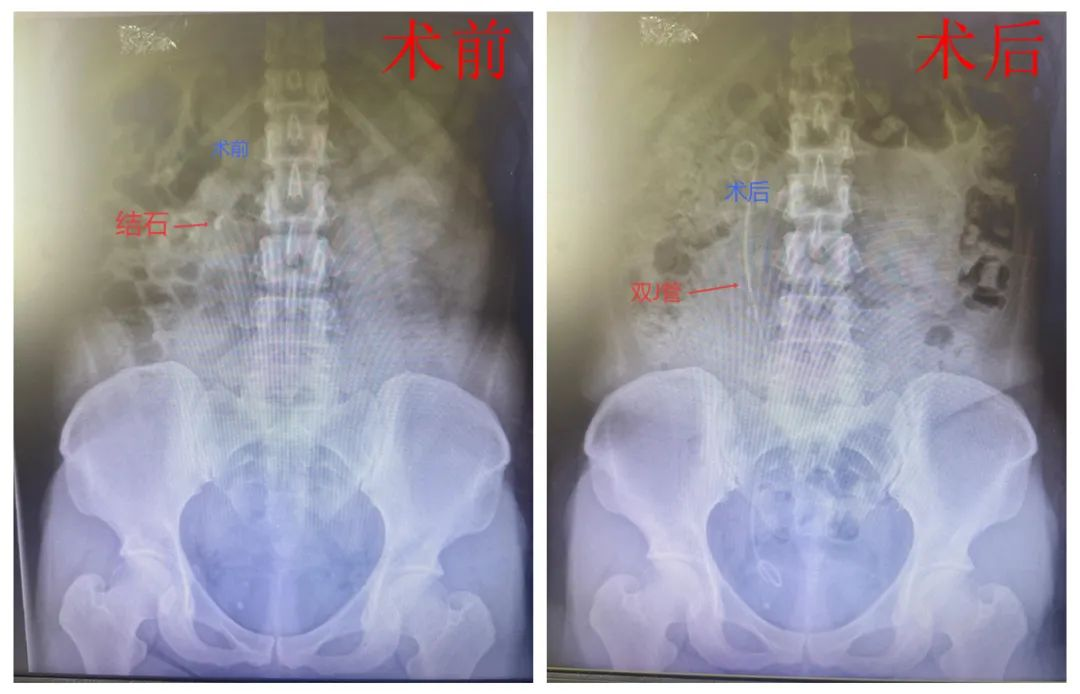

泌尿系统结石作为全球性健康问题,其发病率正随生活方式改变呈上升趋势。42岁的林女士因长期饮水不足、憋尿导致右侧输尿管结石,出现腰腹痛、恶心呕吐、高热等症状。经检查确诊为输尿管梗阻伴肾积水,肾功能受损。在我院接受输尿管软镜碎石术(FURS)并置入双J管。术后症状缓解,虽有轻微血尿和尿频等不适,但经多饮水、避免剧烈运动等护理后恢复良好。一月后拔管复查显示输尿管通畅,肾功能恢复正常。出院随访后得知林女士养成了多喝水、定时排尿的习惯,对微创治疗效果满意。

▲患者术前术后对比图